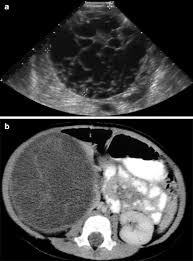

Kidney Cysts Vs Cancer. A tumor can be benign or cancerous malignant. While certain types of cancer can cause cysts cysts themselves are almost always benign.

Similar non inherited mutations can lead to kidney cancer just by sheer accident out of the blue due to aging environmental insults and so on. The cyst is usually characterized by round pouch of thin walled smooth tissue filled with fluid. Hence it is very important to have a clear identification between them. While certain types of cancer can cause cysts cysts themselves are almost always benign.